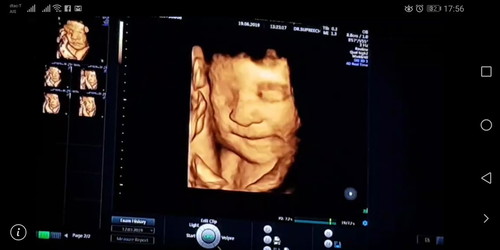

❤️ เบบี้น้อยของแม่... คุยกันก่อนออกจากบ้านว่า.. หาหมออย่าหลับนะลูก >> ผลที่ได้คือ.. #ยิ้มหวานสู้กล้องสุดพลัง ทะเล้นแท้หล่าน้อย #ลูกสาว

34week 3 day จ้า